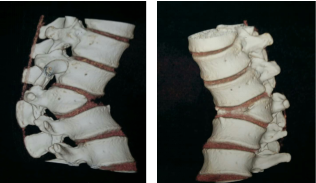

3.先天性椎体发育不良,先天性半椎体会造成脊柱后突畸形,影响患者美观,驼背明显,后背常感疼痛,如畸形明显可能有下肢神经症状,及时采用手术干预,解除脊髓压迫,融合固定,矫正畸形,能取得良好的治疗效果。附典型案例如下: